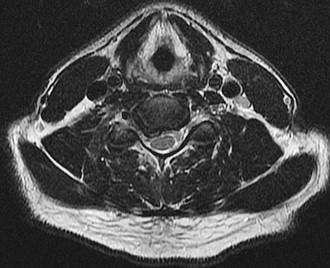

A 65-year-old male presents with progressive clumsiness in his hands, difficulty buttoning his shirt, and a wide-based gait. Physical exam reveals a positive Hoffmann's sign bilaterally.

MRI of the cervical spine demonstrates multilevel degenerative spondylosis with cord compression. Which of the following MRI findings is considered the strongest independent predictor of a poor neurologic recovery following surgical decompression?